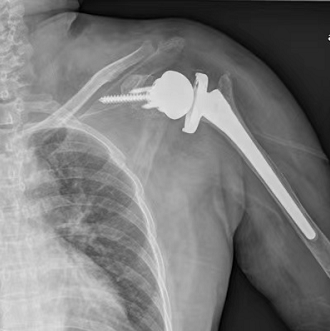

除了破坏关节以外,骨结核给康女士还带来了严重的肩袖损伤,但传统的肩关节假体是根据人体解剖结构设计的,想取得比较理想的效果往往需要患者的肩袖功能完整?!跋裉终飧龆?,主要就是依靠肩袖功能实现,如果肩袖损伤,即使做了传统的肩关节置换术也很难再抬起手来,”姜文学说,“只有反置式肩关节置换术能挽救一部分功能?!?/p>

反置式肩关节假体的许多细节与人体解剖结构相反,旋转中心向内向下偏移,这一设计延长了三角肌、抬高了力臂、增加了力矩,能最大限度地发挥三角肌的功能代偿患者肩袖功能的不全。

1月28日康女士的手术中,姜文学需要考虑到所有的细节:如果旋转中心太靠上,活动中假体就会容易撞到肩胛骨;肩胛骨本就是松质骨,加之康女士长期疼痛活动受限,她的左肩骨质疏松,骨钉必须打到肩胛骨最结实的地方,否则不一定能钉??;肩胛骨是薄薄一片“趴”在肩上的,如果安装太深或者方向有一点偏差,可能骨钉会顶到胸腔甚至肺部。

姜文学形容这台手术:“细致到了要计较2-3毫米的差距。”

在姜文学团队两个半小时的努力下,康女士的手术最终顺利完成,目前她的手已经能抬高70-80度,可以完成洗头、梳头一类的动作,近期即将出院。姜文学介绍,出院后康女士大约需要进行2-3个月的康复训练。